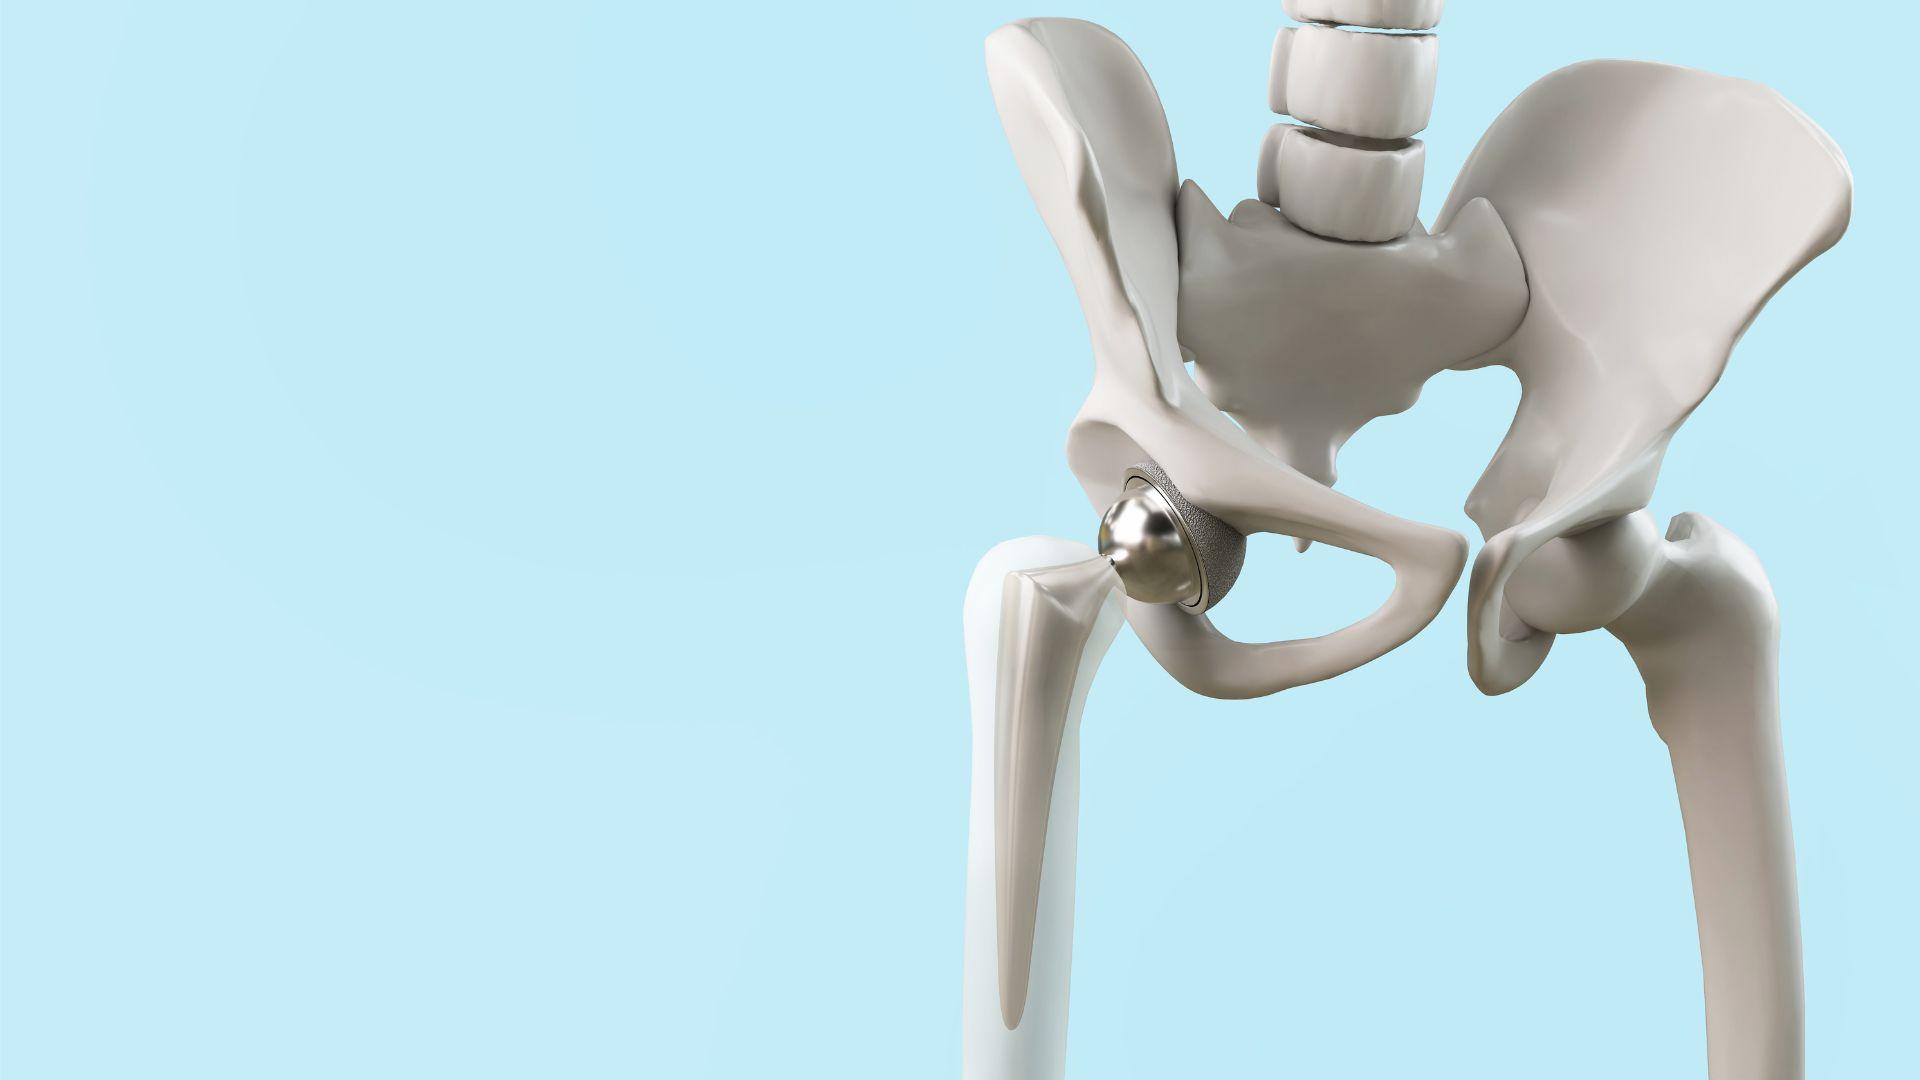

髋关节是一个大的球窝关节。关节的杯侧称为髋臼,球侧称为股骨头。髋关节全关节置换术使用的人工关节包括臼杯、球体和股干,物料通常是合金、聚乙烯或陶瓷等。如果有一个或以上的髋关节损坏,医生便可能会建议进行此手术。